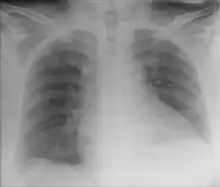

| Chest X-ray showing obvious Chilaiditi's sign, or presence of gas in the right colic angle between the liver and right hemidiaphragm. | |